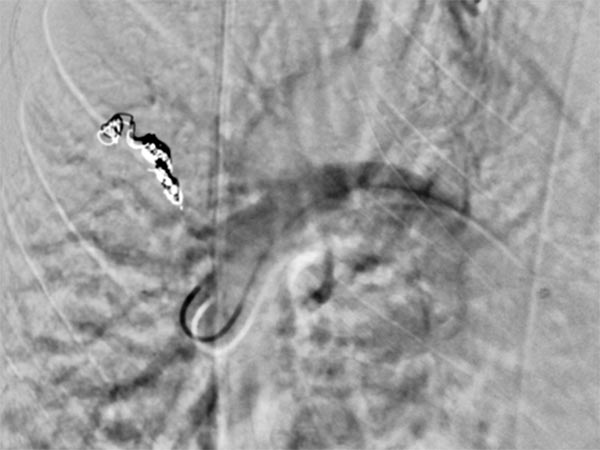

Nach Sondierung der größeren pulmonalen AVM zeigt sich ebenfalls eine für den Morbus Osler typische Dilatation der direkten arteriovenösen Kommunikation in Form eines Aneurysmas. Der venöse Abstrom ist stark dilatiert, damit ist die Gefahr einer Embolie besonders groß.

Die zuführenden Arterien werden mit mehreren Coils verschlossen. Zur sicheren Verankerung werden Teile der Coils in die arterielle Aufzweigung gelegt (Anker-Technik). Die pulmonale AVM ist verschlossen. Im ehemaligen Aneurysma steht noch etwas Kontrastmittel von einer vorherigen Injektion.